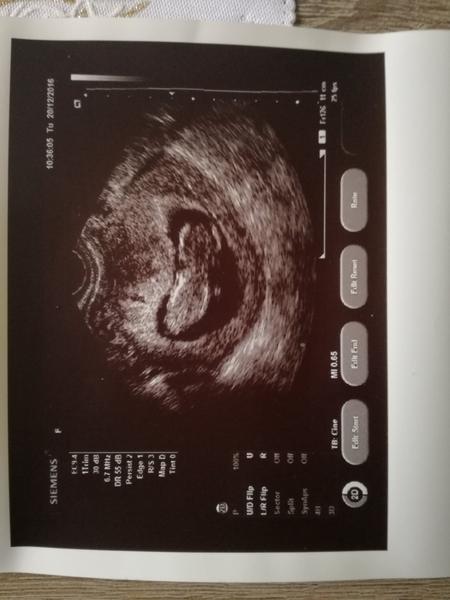

Ahojte tak aj ja sa pridávam som momentálne 9tt+3dni........termín podľa poslednej menštruácie vychádza na 9. júla no doktor povedal, že možno o týždeň dva neskôr, v januári vraj upresní 🙂 s priateľom sme šťastní ako blchy z malej bublinky 🙂 🙂

@lilianna1xs ja som mala naposledy MS teda 22.10.16, kedze mam pravidelny cyklus a meskalo mi to hned som robila test 24.10 kedy sa ukazal iba taky duch druhej ciarocky na teste...hned nato som sla 27.10 ku doktorovi kde na uktrazvuku videl len nejaku malinku bodku...zobral mi krv hned v ten den ale vysli len zvysene hodnoty HCG ale nie 100% potvrdzujuce, preto som sla na krv este raz 1.11 a uz to bolo stopercentne potvrdene, dva tyzdne potom som bola na dalsom ultrazvuku kde uz bilo srdiecko v tej mini bodocke...doktor povedal, ze dalsi termin na ultrazvuk mam az 13.1.2016 kedy mi da aj tehotensku knizku a urci aj termin porodu podla velkosti plodu, takze termin 29.7.2016 sopm si vypocitala sama podla kalkulacky na internete...sama pocitam, ze som momentalne v 9 tyzdni, napinanie na vracanie mam pocas celého dna a prsia ma neskutocne bolia, k tomu ma chyta nejaka depka z toho vsetkeho...aaaaach

Ahojte, tak uz mam poradnu zasebou. Vsetko je v poriadku. Som 12tt+1 podla USG. Malicke je 56,1mm velke a veeelmi aktivme 😀 Odbery mi budu robit az 18.1. a vtedy dostanem aj teh.knizku. Mam len trocha vyssi tlak preto mi dal magne b6.